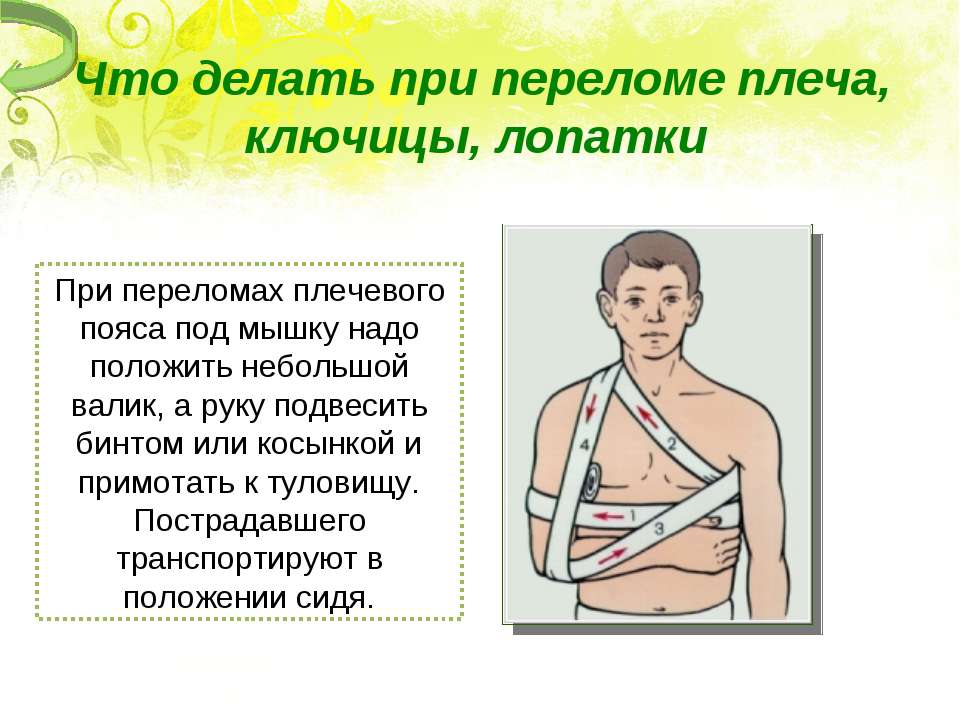

Вывихи и переломы ключицы презентация - 85 фото